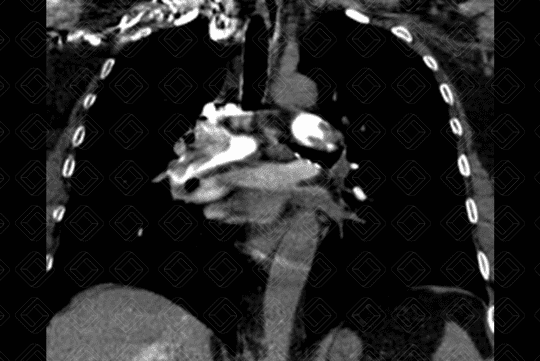

Descrição das imagens: Angiotomografia computadorizada do tórax com aquisições axiais e coronal, evidenciando tromboembolia pulmonar maciça com “êmbolo em sela” (seta vermelha) nas artérias pulmonares principais.

• Angiotomografia computadorizada do tórax: Padrão-ouro para o manejo do TEP agudo. Este exame é sempre realizado após a administração do meio de contraste. O principal sinal é a falha de enchimento, formando um ângulo agudo com a parede do vaso, delimitada pela substância contrastante (figura 1).